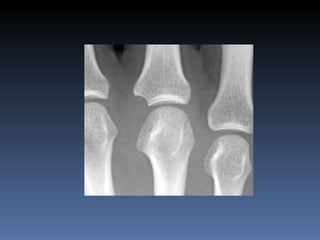

Gota Asimetrica Mas comun en la 1a.  articulacion M.T.T.F. Es comun la bursitis del olecranon Erosiones con bordes sobresalientes (mordedura de rata) Edema de partes blandas Depositos con densidad de tejidos blandos (tofos)

Gota Asimetrica Mascomun en la 1a. articulacion M.T.T.F. Es comun la bursitis del olecranon Erosiones con bordes sobresalientes (mordedura de rata) Edema de partes blandas Depositos con densidad de tejidos blandos (tofos)